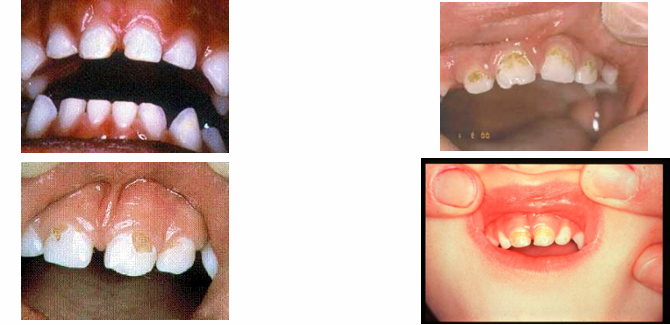

early signs of decay

-white spot lesions

-not as visible when dry → become chalky

later signs of decay

-enamel breakdown

advanced/severe decay

-decay that extends all the way to the gingiva anteriorly or very extensively occlusally in the posterior